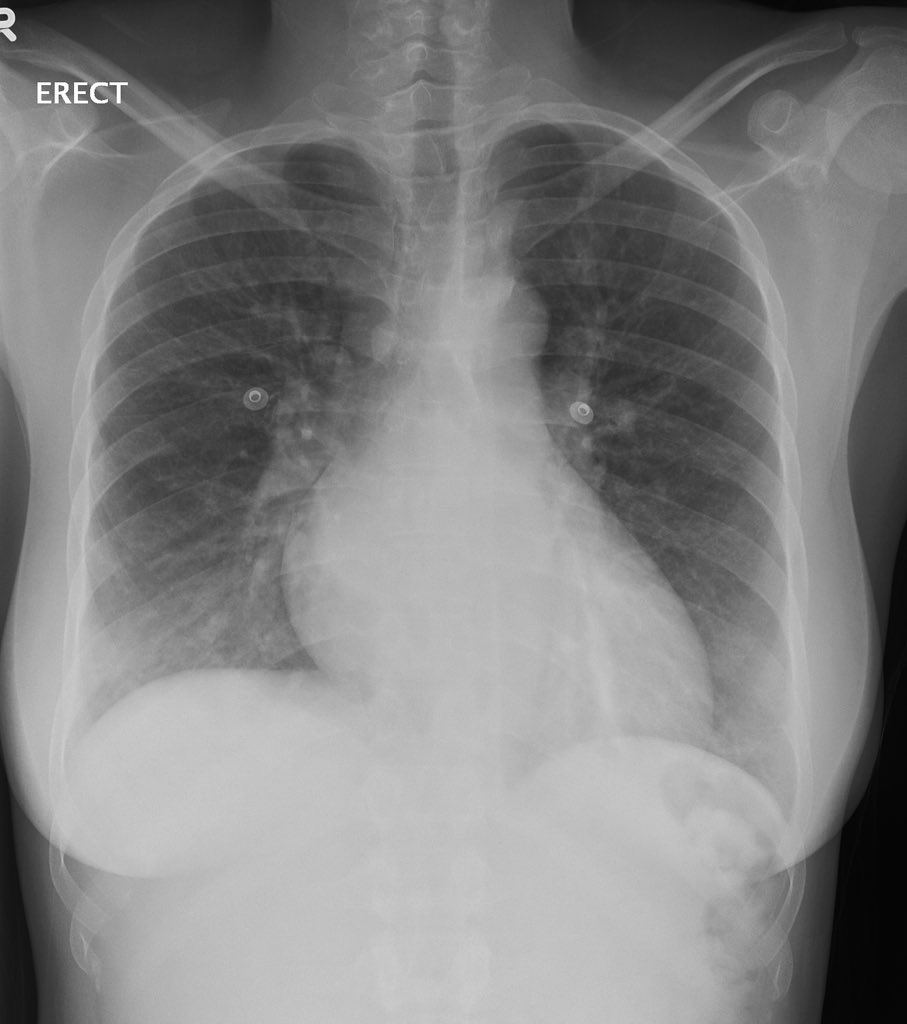

6️⃣Acute chest syndrome